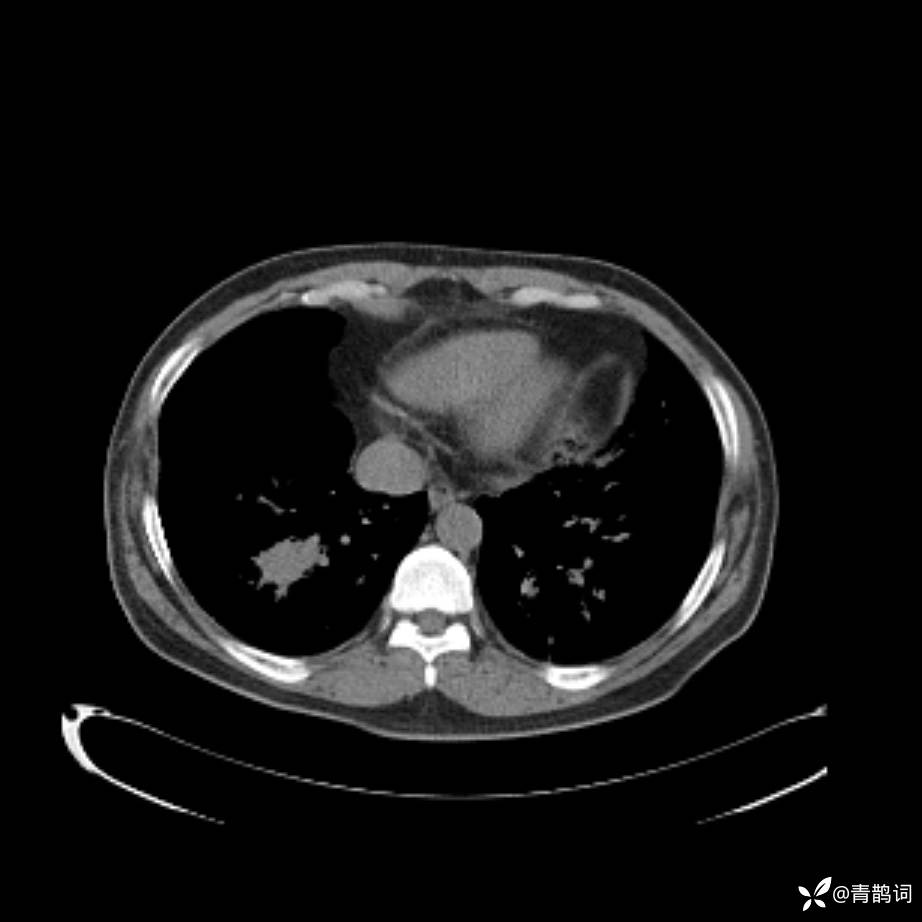

患者年龄:30岁。

患者性别:男。

简要病史:左颜面部肿胀2年,反复咳嗽咳痰,逐渐加重。

结合病史及影像学表现,期待评论区各位老师各抒己见~

木村病 (14)